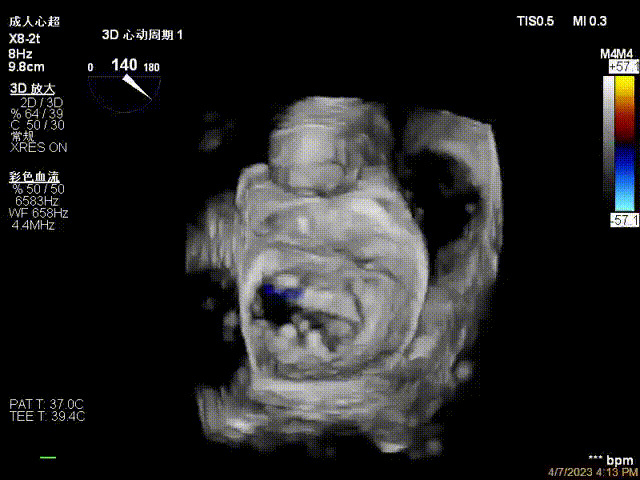

術后超聲顯示二尖瓣反流消失,瓣膜夾穩定

接受治療的是一例器質性重度二尖瓣反流(DMR)患者,主訴“反復活動后胸悶,氣促3年余”。術前超聲顯示,雙房增大,二尖瓣脫垂伴重度反流,輕度三尖瓣反流,輕度肺高壓,升主動脈增寬。手術經股靜脈-房間隔入路,采用全身麻醉插管,在TEE和DSA引導下完成房間隔穿刺。置入JensClip瓣膜夾系統后,在左房調整瓣膜夾的位置和軸向,后進入左室,在TEE引導下捕捉二尖瓣前后瓣葉,并關閉瓣膜夾。經TEE反復確認手術效果后最終鎖定并釋放瓣膜夾。術后即刻超聲顯示瓣膜夾位置穩定,功能良好,術前二尖瓣反流4+,術后0反流,肺靜脈逆流和左房壓都顯著好轉,手術圓滿成功(以上數據都來源于醫院的臨床記錄)。術后患者狀態良好,目前已安排出院。